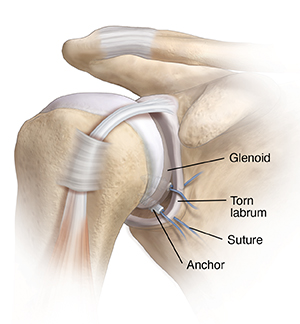

Torn labrum

The shoulder is a ball and socket joint. The labrum normally supports and cushions the shoulder joint. In a torn labrum, the socket that the ball (the upper end of your arm) fits into isn't very deep. The shallow socket raises the chance for instability.

The labrum may tear off the rim of the glenoid. This can cause the joint to catch or feel like it’s slipping out of place. The shoulder may even dislocate.

A torn labrum is fixed by reattaching it to the glenoid. This is often done with special anchors put into the glenoid bone. Stitches attached to the anchors are tied to hold the labrum in place. The joint is then more stable.